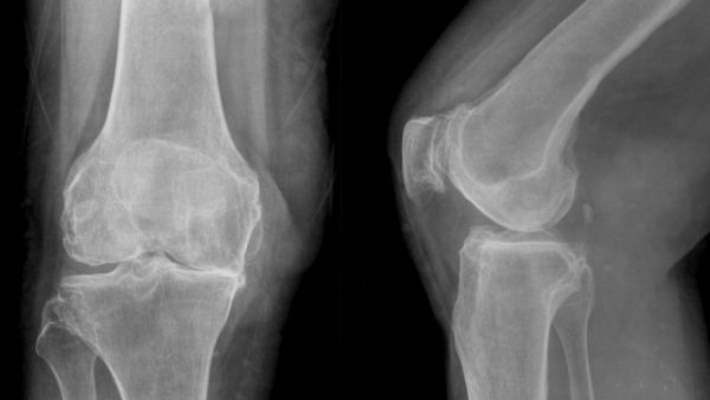

Osteoartrit Sebepleri